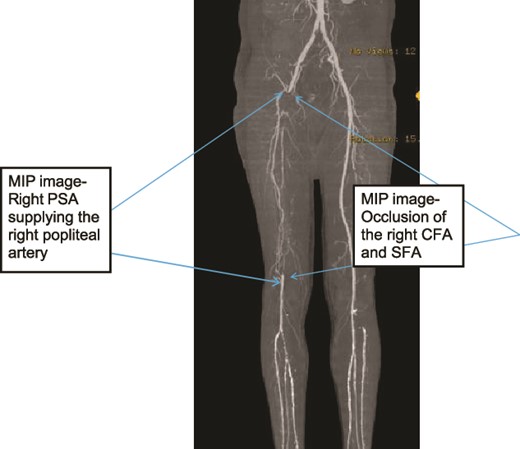

A 45-year old known diabetic and hypertensive male patient presented with right foot pain of one year. He had right calf claudication for 4 years and associated darkening of the right little toe of 1 month. He was a cigarette smoker for 15 years, but had discontinued 1 month prior. On examination, he had right fifth digit dry gangrene with non-palpable pulses in the right popliteal artery (PA), dorsalis pedis artery (DPA), or posterior tibilias artery (PTA). Preoperative ABI was not recordable (no flow detected in DPA or PTA with handheld Doppler ultrasound). Doppler ultrasound showed ~90% occlusion of right common femoral artery (CFA) with hemodynamically significant downstream insufficiency and scattered foci of arterial wall calcification and wall thickening of bilateral LL arteries. CTA showed mild atherosclerotic disease, long segment right CFA, superficial femoral artery (SFA), proximal profunda femoris (PF), proximal and mid right PA occlusion and right PSA supplying collateral to the distal PA with right tibio-peroneal trunk atherosclerotic occlusion (Figs 1–3). Patient underwent right CFA thrombectomy and femoro-popliteal (supragenicular) bypass using ipsilateral subcutaneously tunneled reversed great saphenous vein (GSV). Postoperative ABI was 1.2 and he was discharged on Per Os (PO) anticoagulant (Rivaroxaban). On a 3-year postop follow up, patient had mild claudication with no rest pain or wounds.

Case 1—3D-Maximum Intensity Projection image of LL CTA frontal view of the bilateral LL arteries showing long segment occlusion of the right CFA and right SFA; right PSA supplying the right popliteal artery.